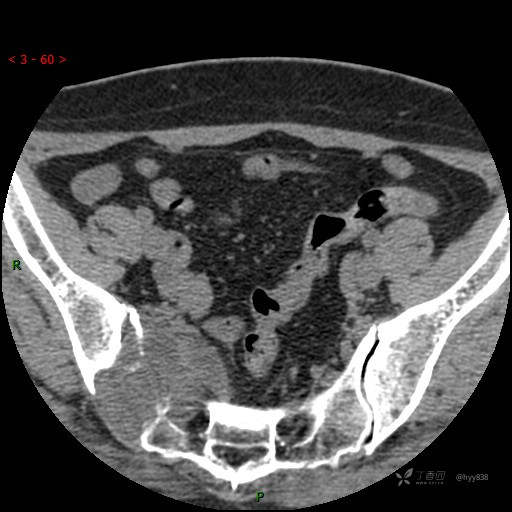

骶髂关节CT平扫